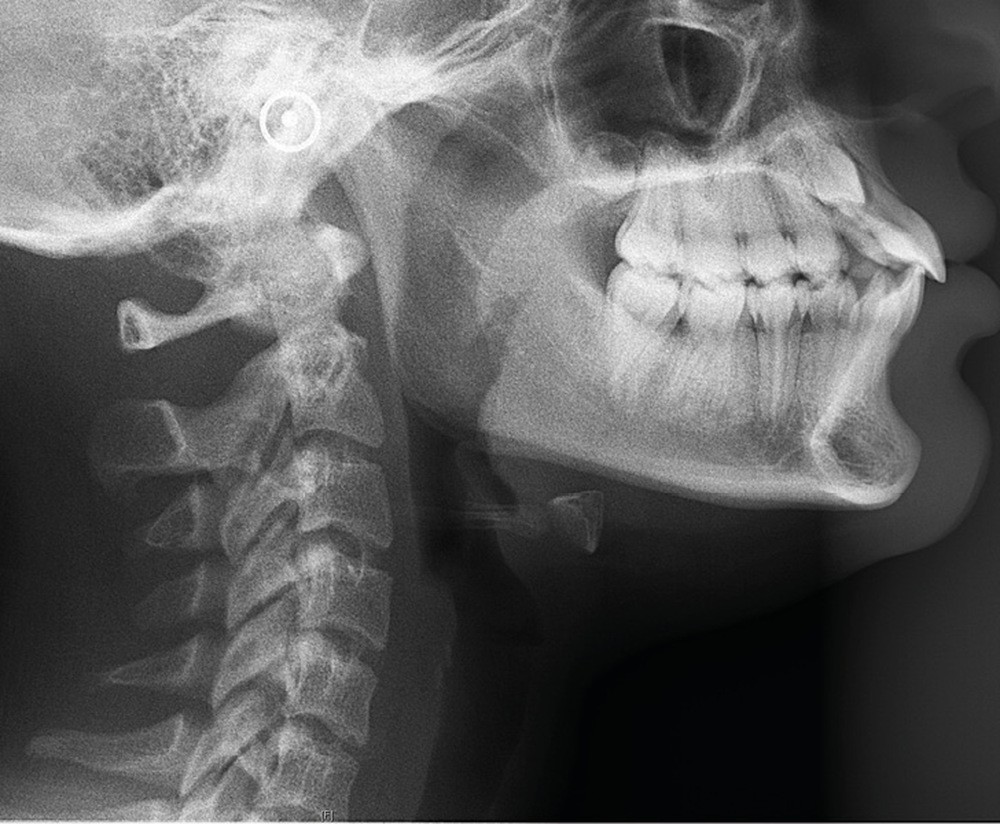

La patiente âgée de 14 ans et 6 mois le jour du bilan se présente en consultation pour une gêne esthétique au niveau de ses dents maxillaires : « trop en avant et avec des espaces ».

Les examens cliniques et radiologiques ont mis en évidence l’inclusion de 13 et 23, une légère classe II bilatérale par perte d’ancrage, un biotype parodontal de type IV de Maynard et Wilson avec une insertion du frein mandibulaire antérieur papillaire, une biproalvéolie et une typologie hypodivergente. La réalisation d’un examen tridimensionnel a permis de confirmer la localisation palatine de 23 et vestibulaire de 13 ainsi que de visualiser l’étendue des résorptions radiculaires touchant 12, 21 et 22 (fig. 1a-i).